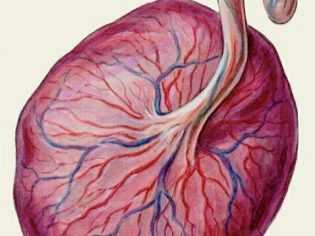

Пуповина или, как ее еще могут называть, пупочный канатик представляет собой удлиненный жгутик, внутри которого проходят кровеносные сосуды. Они необходимы для того, чтобы плод во время своей внутриутробной жизни получал все необходимые питательные вещества для роста и развития. Нормальный пупочный канатик выглядит как серо-синий тяж, который прикрепляется к плаценте. В норме он формируется на самом раннем сроке беременности и продолжает развиваться вместе с растущим малышом.

В норме артериальные сосуды, которые находятся в пуповине, покрыты вартоновым студнем. Это студенистое вещество защищает артерии и вены, которые имеются в пуповине, от различных повреждений. При оболочечном прикреплении пуповины к плаценте кровеносные сосуды не на всем своем протяжении покрыты вартоновым студнем. Это способствует тому, что риск развития различных травматических повреждений артерий и вен достаточно высокий.